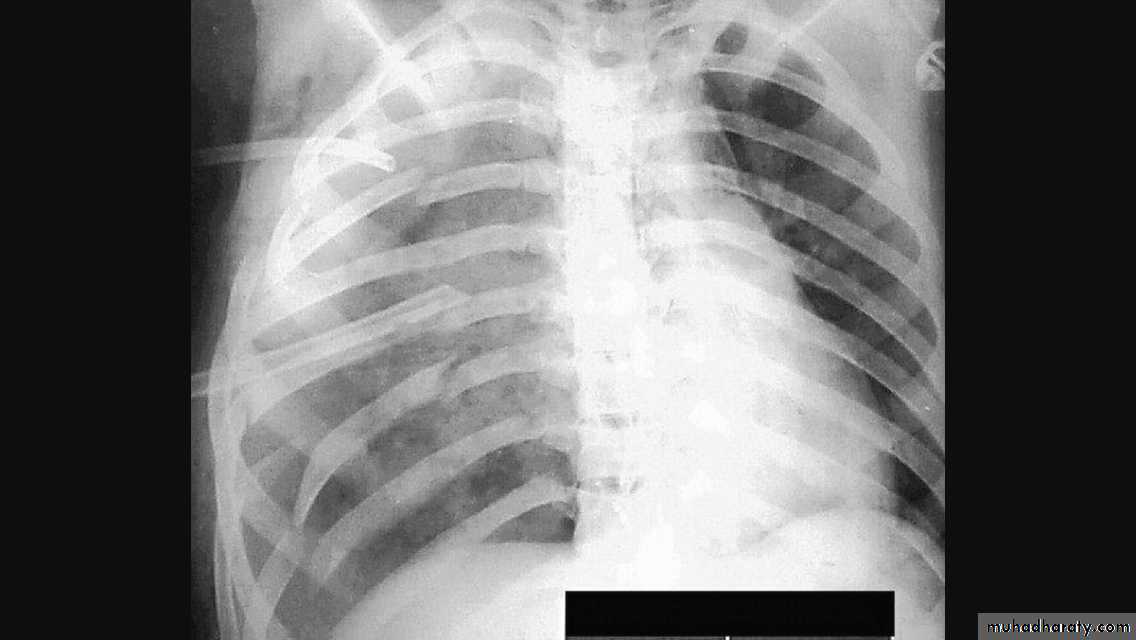

Radiopaque hemi-thoraxPneumothorax (air in pleural space )

Signs

Loss of vascular markings at the outer parts of lung fieldsDemarcating pleural line between the lung & vessels lacking area.

Well demarcating of the scapula

Epsilateral lung collapse

Tension pneumothorax

Emergency condition

Pressure effect on the mediastinum & major vessels

Treatment by chest tubes